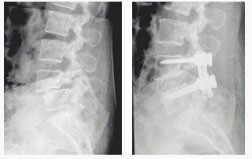

후방 요추체간 유합술 (PLIF) : 광범위한 후방 감압술 후 추간판(디스크)을 제거한 후 골이식을 시행하여 추체간 유합을 얻는 것

- 후외방 유합술에 비해 절개가 적다

- 신경근에 대한 충분한 감압이 이루어진다

- 추간판(디스크)로 인한 동통 및 재발이 없다

- 추간판 높이를 정상으로 회복시켜 준다

- 척추 정렬을 정상으로 회복시켜 준다

* 현재에는 최소 침습적인 방법으로 적은 절개를 통해 가능하다

전방 요추체간 유합술 (Anterior Lumbar Interbody Fusion)

- 수술시 출혈이 적다.

- 수술 창상이 적다

- 수술 후 조기보행이 가능

- 수술 후 인접 척추체에 영향이 적다